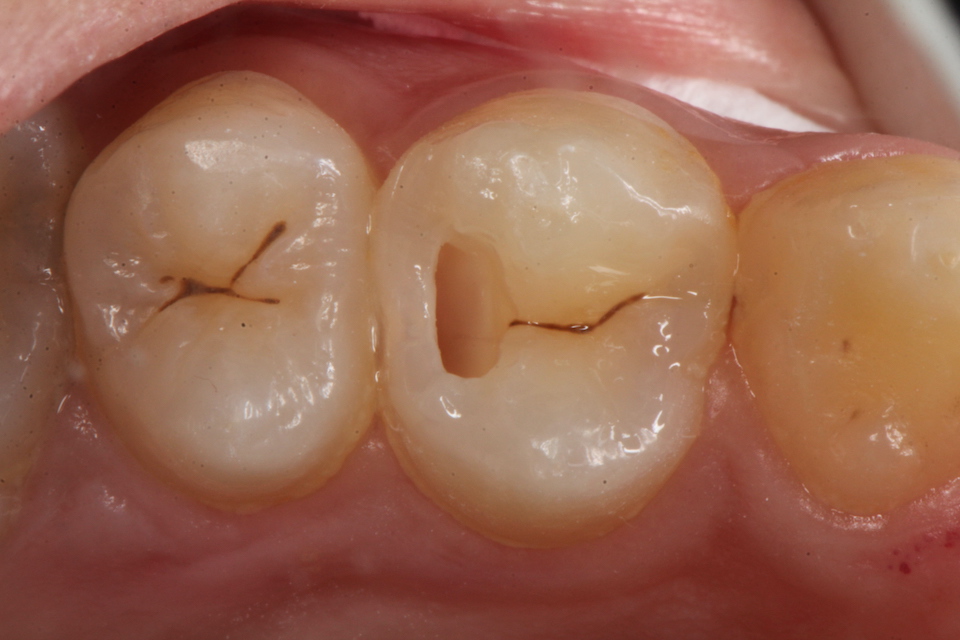

下顎7番の頬側歯茎部カリエスの原因 2025.06.04